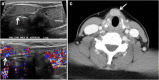

Focal and diffuse thyroid abnormalities are commonly encountered during the interpretation of computed tomography (CT) exams performed for various clinical purposes. These findings can often lead to a diagnostic dilemma, as the CT reflects the nonspecific appearances. Ultrasound (US) examination has a superior spatial resolution and is considered the modality of choice for thyroid evaluation. Nevertheless, CT detects incidental thyroid nodules (ITNs) and plays an important role in the evaluation of thyroid cancer. In this pictorial review, we cover a wide spectrum of common and uncommon, incidental and non-incidental thyroid findings from CT scans. We also discuss the most common incidental thyroid findings, best practices for their evaluation, and recommendations for their management. In addition, we explore the role of imaging in the assessment of thyroid carcinoma (before and after treatment) and preoperative thyroid goiter, as well as localization of ectopic and congenital thyroid tissue.

Teaching points: • Thyroid disorders tend to have non-specific CT appearances. • ITNs are common on neck CT. • ITN management depends on nodule size, age, health status, lymphadenopathy, and invasion. • CT is used in assessment of cancer extension, mass effect, invasion, and recurrence. • CT plays a role in preoperative planning in patients with symptomatic goiter.